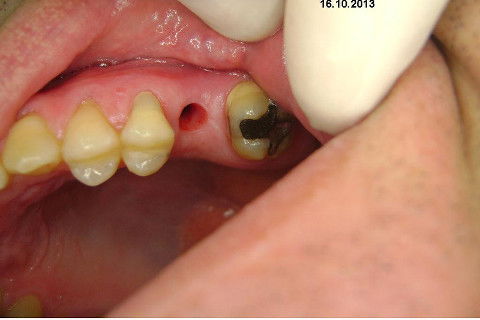

Instalação de um implante em região do 26. Utilizamos um implante cone morse Alvim Neodent 4.3 X 11,5. Foi uma cirurgia muito rápída e minimamente traumática, sem retalho e sutura.